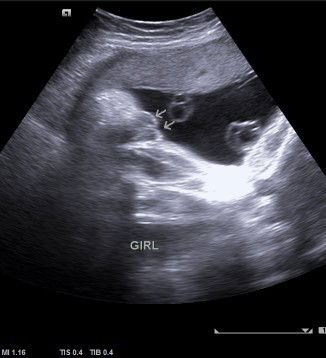

Hai mommy semua. .saya mula² scan baby 19 week dan 25 week doktor ckp baby boy. .dan saya scan semula 30 week doktor ckp baby girl pulak. .apa pendapat mommy semua bila lihat gambar scan yang saya share ni. .

Jantina baby

Hai mommy semua, saya scan baby 30 minggu. .betul ke gambaran tu menunjukan baby girl??

Baby gender